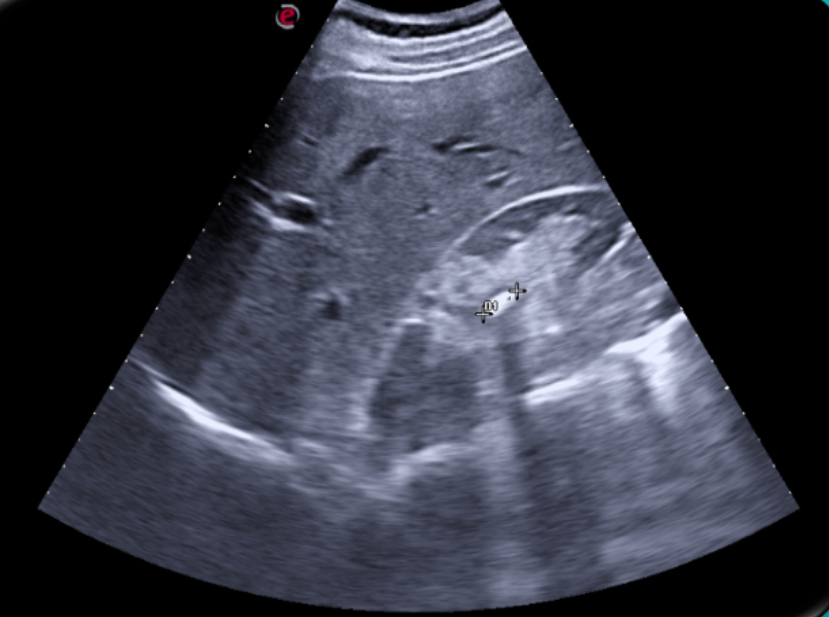

Expondremos la utilidad de la EC como herramienta en el manejo de los pacientes con diferentes tipos de dolor que atiende el Médico de Familia en las consultas diarias, urgentes, e incluso en los domicilios, en diversos escenarios clínicos a los que podemos enfrentarnos en nuestra práctica clínica habitual, desde un dolor visceral (abdominal, torácico, urológico o ginecológico), un dolor músculo-esquelético (traumático o no, con sospecha de fractura u osteoartrósico incapacitante), un dolor vascular (sospecha de trombosis venosa profunda, trombosis arterial aguda, aneurismático); ayudando a obtener una información crucial con un método no invasivo que nos ayudará a reducir la incertidumbre y orientar mejor el diagnóstico de nuestros pacientes e incluso nos podrá ser muy útil como herramienta con fines terapéuticos como en el caso de las infiltraciones ecoguiadas.